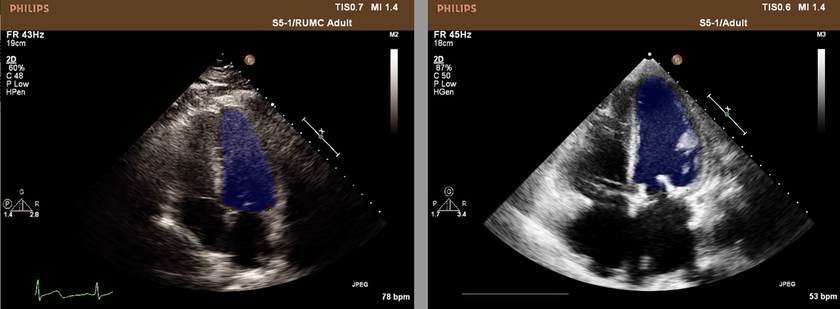

Компания «СКЗ» по заказу израильской клиники ведет разработку ПО, которое поможет определять позиции сердечных клапанов пациентов на снимках УЗИ. В качестве базовой модели выбрана архитектура нейронной сети Unet, часто используемая в задачах обработки биомедицинских изображений. После доработки нейросетевой архитектуры, как рассказали в компании, точность результата превысила 95%.

| | Даже в случае низкого качества полученных снимков, где клапаны сердца не всегда хорошо и отчетливо видны, разработанный классификатор с высокой точностью определит их расположение. Для решения поставленной задачи применен метод семантической сегментации, так как данный метод учитывает не только пространственную, но и контекстную информацию, получаемую со снимка». рассказывает Михаил Смирнов.

| |

В «СКЗ» рассказали, что заказчик планирует установить разработанное ПО на существующие аппараты УЗИ.